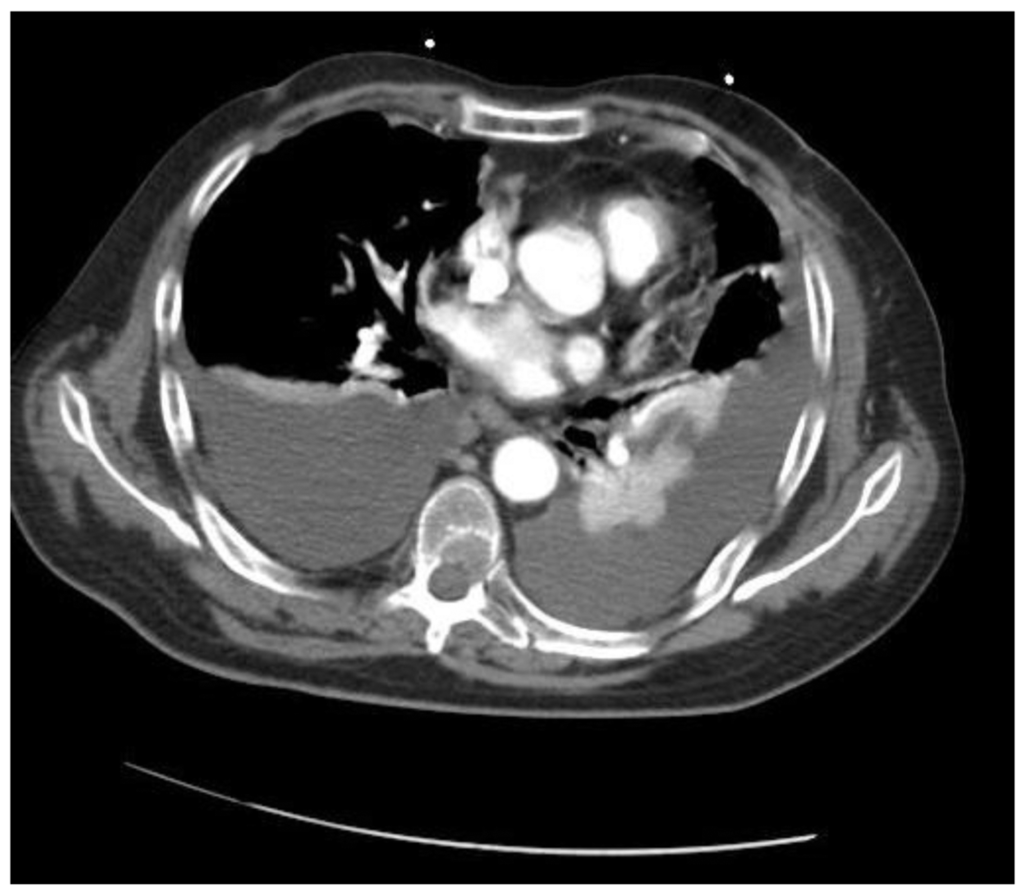

Nine months after the stereotactic biopsy, the patient's clinical status deteriorated; he experienced fatigue, intense back pain involving the dorsolumbar region, worsening alexia. Cranial MRI showed a tumor recurrence and a nitrosourea chemotherapy regimen, fotemustine, was administered (an induction phase of one weekly perfusion of 100 mg/m2 for three weeks, and then up to four cycles of adjuvant fotemustine according to the standard regimen of one 100 mg/m2 perfusion every 28 days after a four-week break). Despite adjuvant chemotherapy, the patient's status worsened and he was hospitalized in emergency in the neuro-oncology department. Agitation and mental confusion were noted and a secondary cancer of the lung was suspected on thoracic CT scan (bilateral pleural effusion, atelectasis of the left inferior lobe, mediastinal nodes, and diffuse pulmonary lesions) (Figure 3). Symptomatic therapy was administered but no aggressive treatment. The patient finally died.